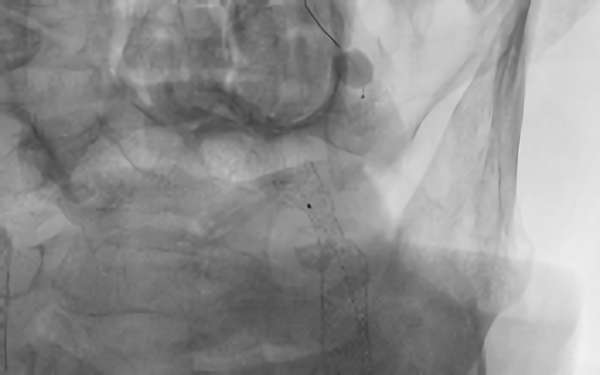

627

'19年9月10日

左内頚動脈狭窄症

80代

院内外来

手術写真

治療

前

中

後

手術日